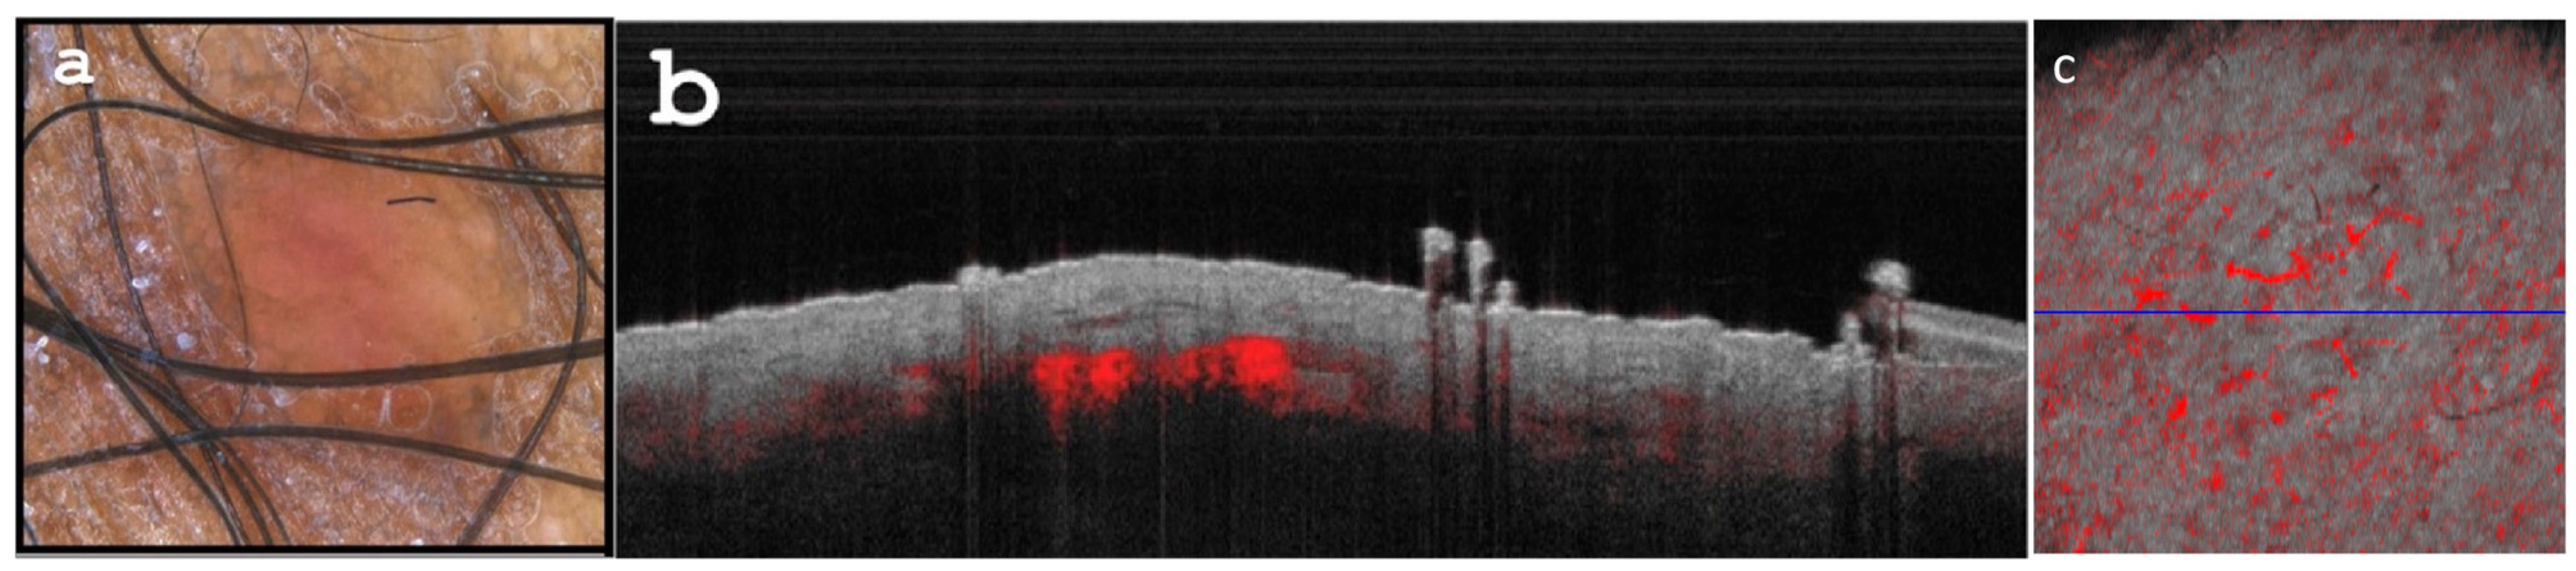

2.1. Case Report 1

2.2. Case Report 2